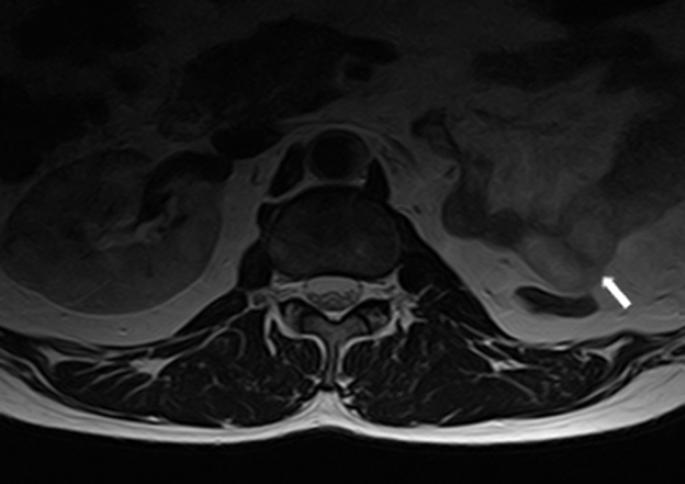

腰椎间盘磁共振成像期间腰椎的偶然椎体外发现。

Incidental extraspinal findings in the lumbar spine during magnetic resonance imaging of intervertebral discs.

To calculate the frequencies of incidental extraspinal findings and incidentally detected congenital anomalies or anatomical differences in the lumbar spine on magnetic resonance imaging (MRI) scans of intervertebral discs.

Of the 379(100%) patients, 90(23.7%) patients were presented with incidental findings. Among the incidental findings, 39(10.3%) were renal cysts, 10(2.6%) were retroverted uteri, 5(1.3%) were Nabothian cysts, 4(1.1%) were ovarian cysts, 10(2.6%) were uterine fibroids, 3(0.8%) were endometrial thickening, 11(2.9%) were indicative of hydronephrosis, 4(1.1%) were uncovered prostatic enlargement, 2(0.5%) were atrophic kidney, and 1(0.3%) each was of an ectopic kidney and bladder wall thickening, respectively.

计算在椎间盘磁共振成像(MRI)扫描中偶然发现的脊柱外异常以及偶然检测到的腰椎先天性异常或解剖差异的发生率。

379例(100%)患者中,90例(23.7%)有偶然发现。在这些偶然发现中,肾囊肿39例(10.3%),子宫后倾10例(2.6%),宫颈纳氏囊肿5例(1.3%),卵巢囊肿4例(1.1%),子宫肌瘤10例(2.6%),子宫内膜增厚3例(0.8%),肾积水11例(2.9%),前列腺增生4例(1.1%),肾萎缩2例(0.5%),异位肾和膀胱壁增厚各1例(0.3%)。